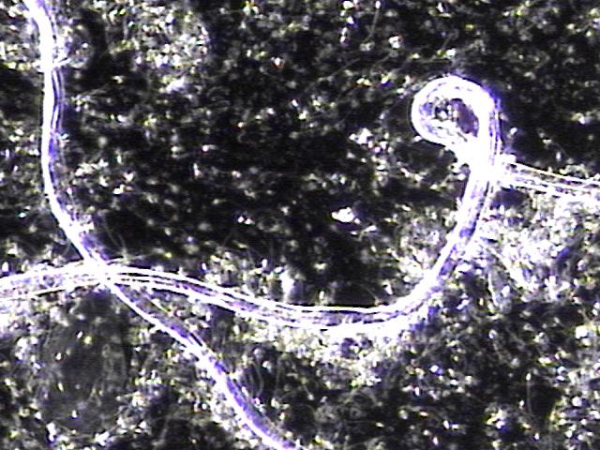

주 2회 전립선과 전립선관, 사정관 입구와 사정관과 정낭 그리고 정관등의 표적 치료후 치료된 현미경학적 자료입니다.

This is a microscopic image taken after twice-weekly targeted treatment of the prostate, prostatic ducts, ejaculatory ducts, seminal vesicles, and vas deferens.

It shows tissue fragments and inflammatory materials that had blocked these passages. Through treatment, these obstructive materials were cleared, helping to improve circulation and function.

This process may support better semen flow and reduce symptoms related to blockage or inflammation.

전립선과 정관 그리고 사정관과 정낭등의 표적 치료후 현미경학적 사진과 윗쪽은 정관에 막혀 있던 치료된 사진과 아랫쪽은 전립선관의 치료된 사진.

Here we see two microscopic images after targeted treatment of the prostate, seminal vesicles, ejaculatory ducts, and vas deferens etc.

- The image on the above appears to show material that was once blocking the vas deferens, now cleared after treatment.

- The image on the below seems to show a treated prostatic duct, where the obstruction has also been resolved.

These findings suggest that the therapy helped improve the passageways involved in semen transport.